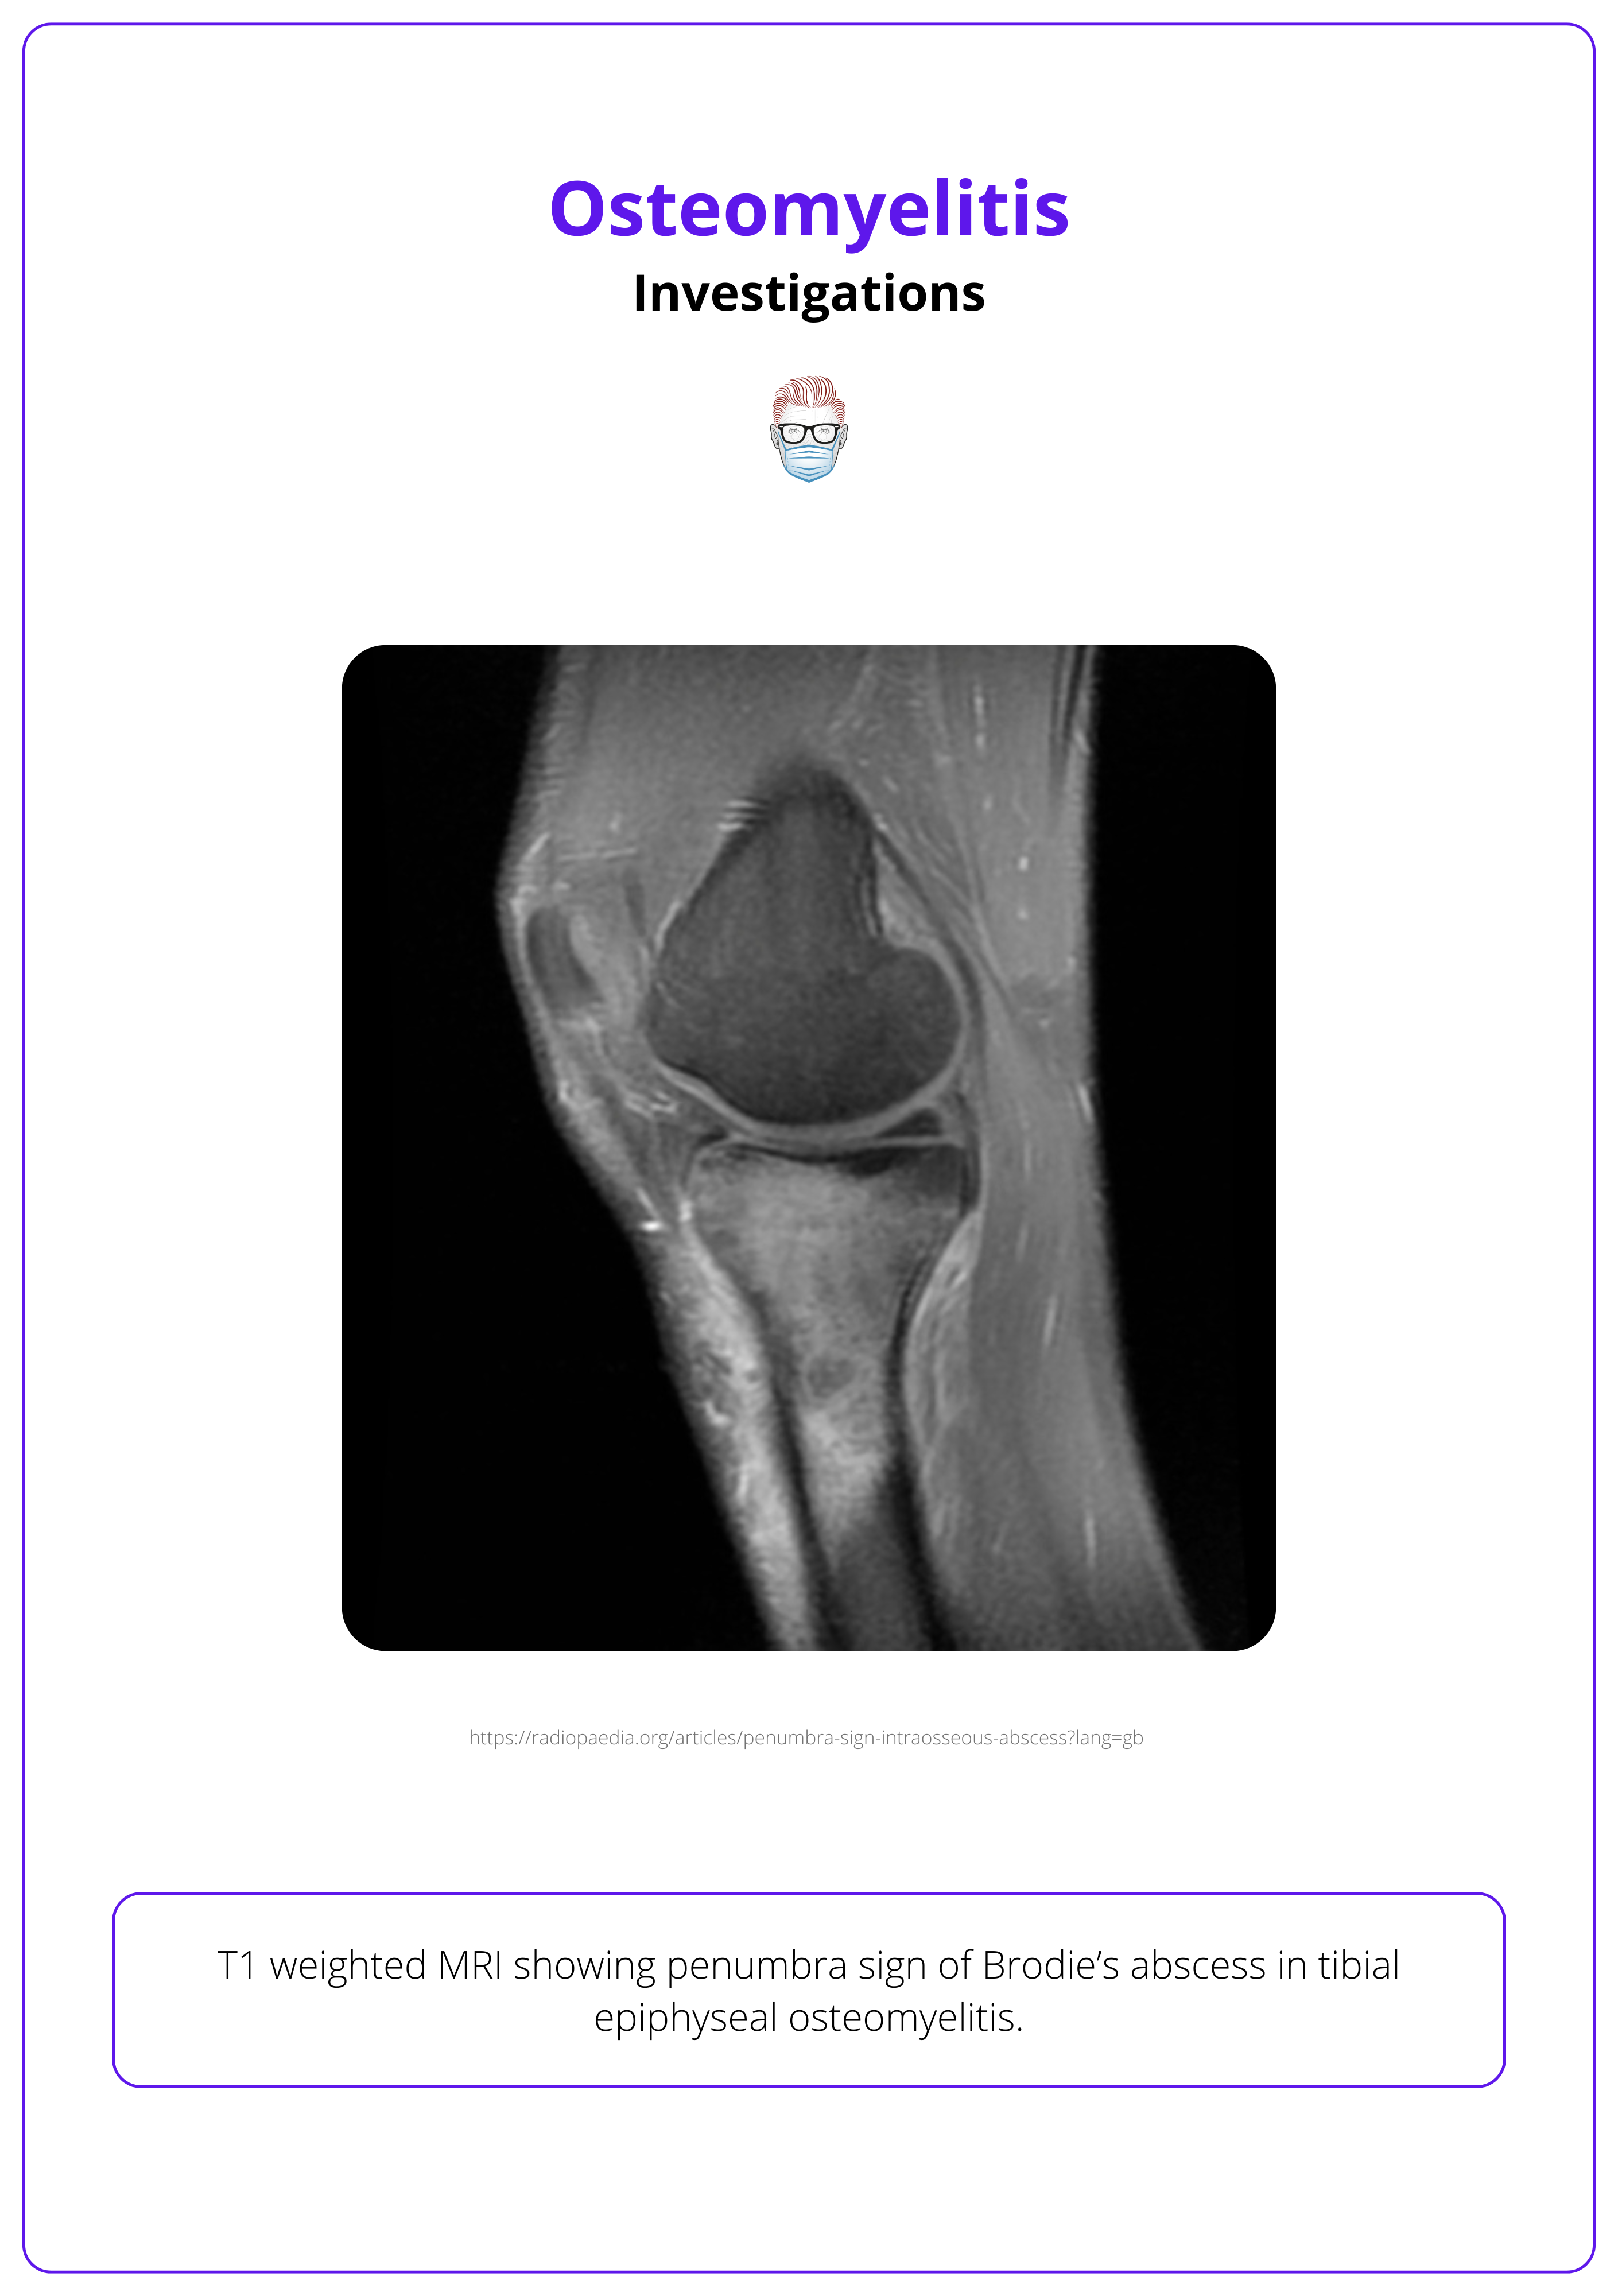

MRI is ideal for early detection and assessing soft tissue involvement. Key signs include:

- Bone Marrow Edema: Detectable within 1-2 days of infection onset.

- Brodie’s Abscess: Intraosseous abscess, common in children near growth plates.

- Penumbra Sign: Seen on T1-weighted MRI as an enhancing rim around an intraosseous abscess, further defined with contrast.

The image below illustrates a T1-weighted MRI of osteomyelitis.